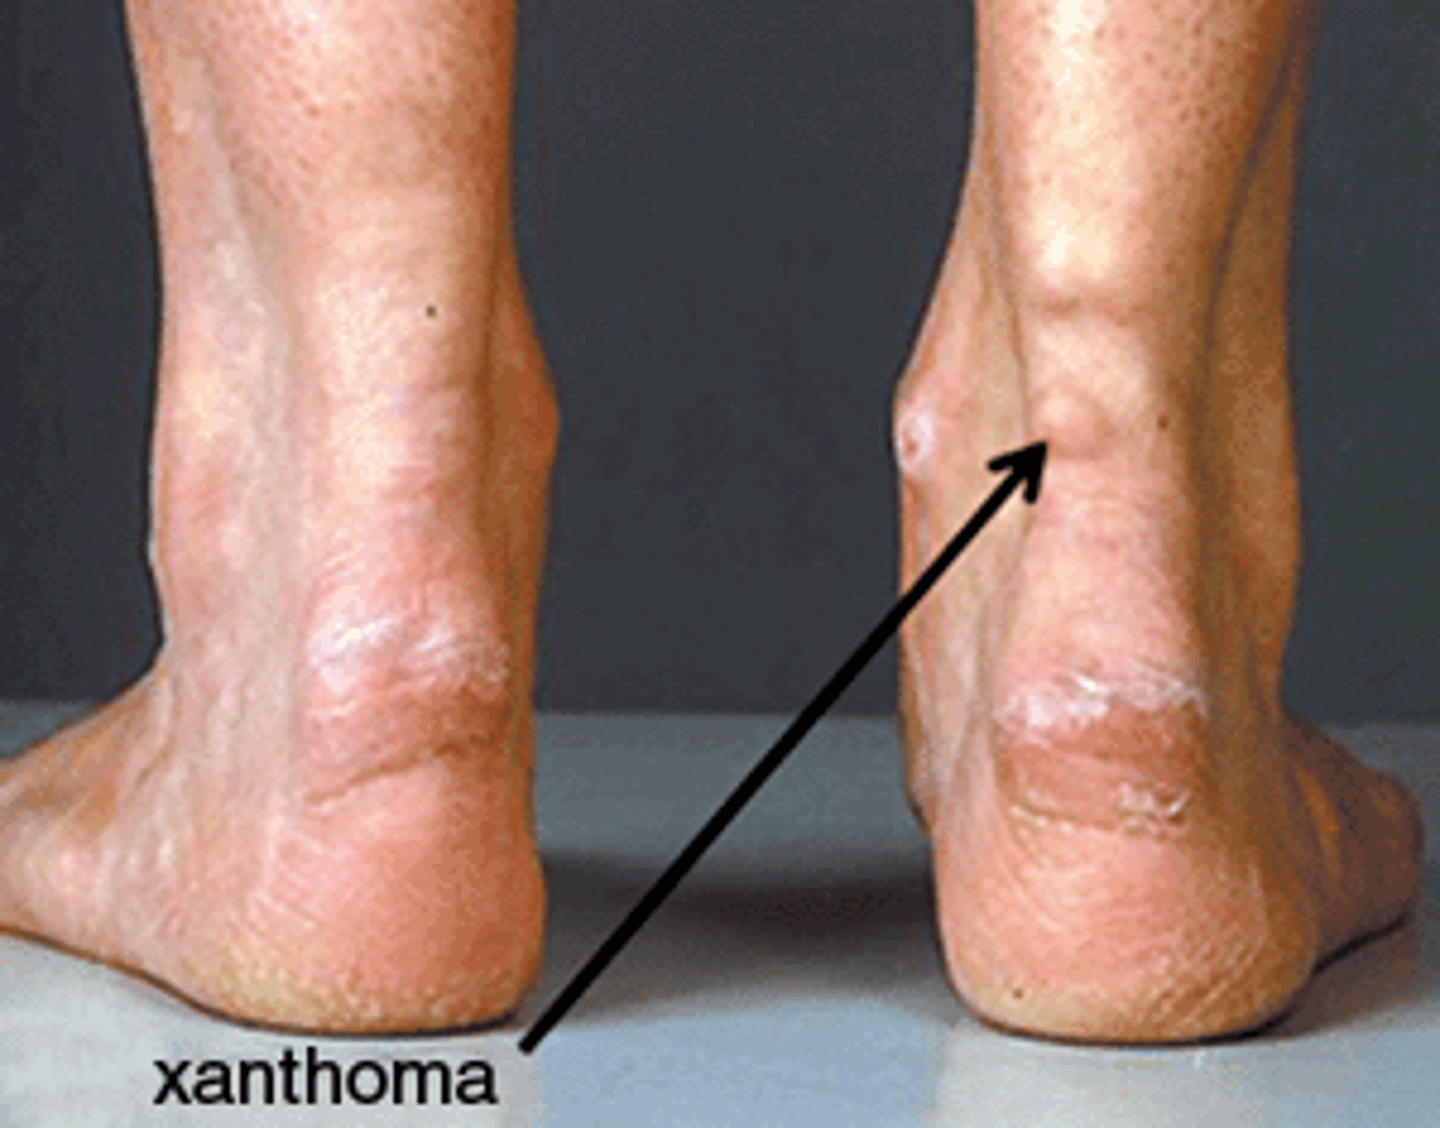

Achilles tendon Xanthoma

Familial Hyper cholesterolemia (low LDL receptor signaling)

AD